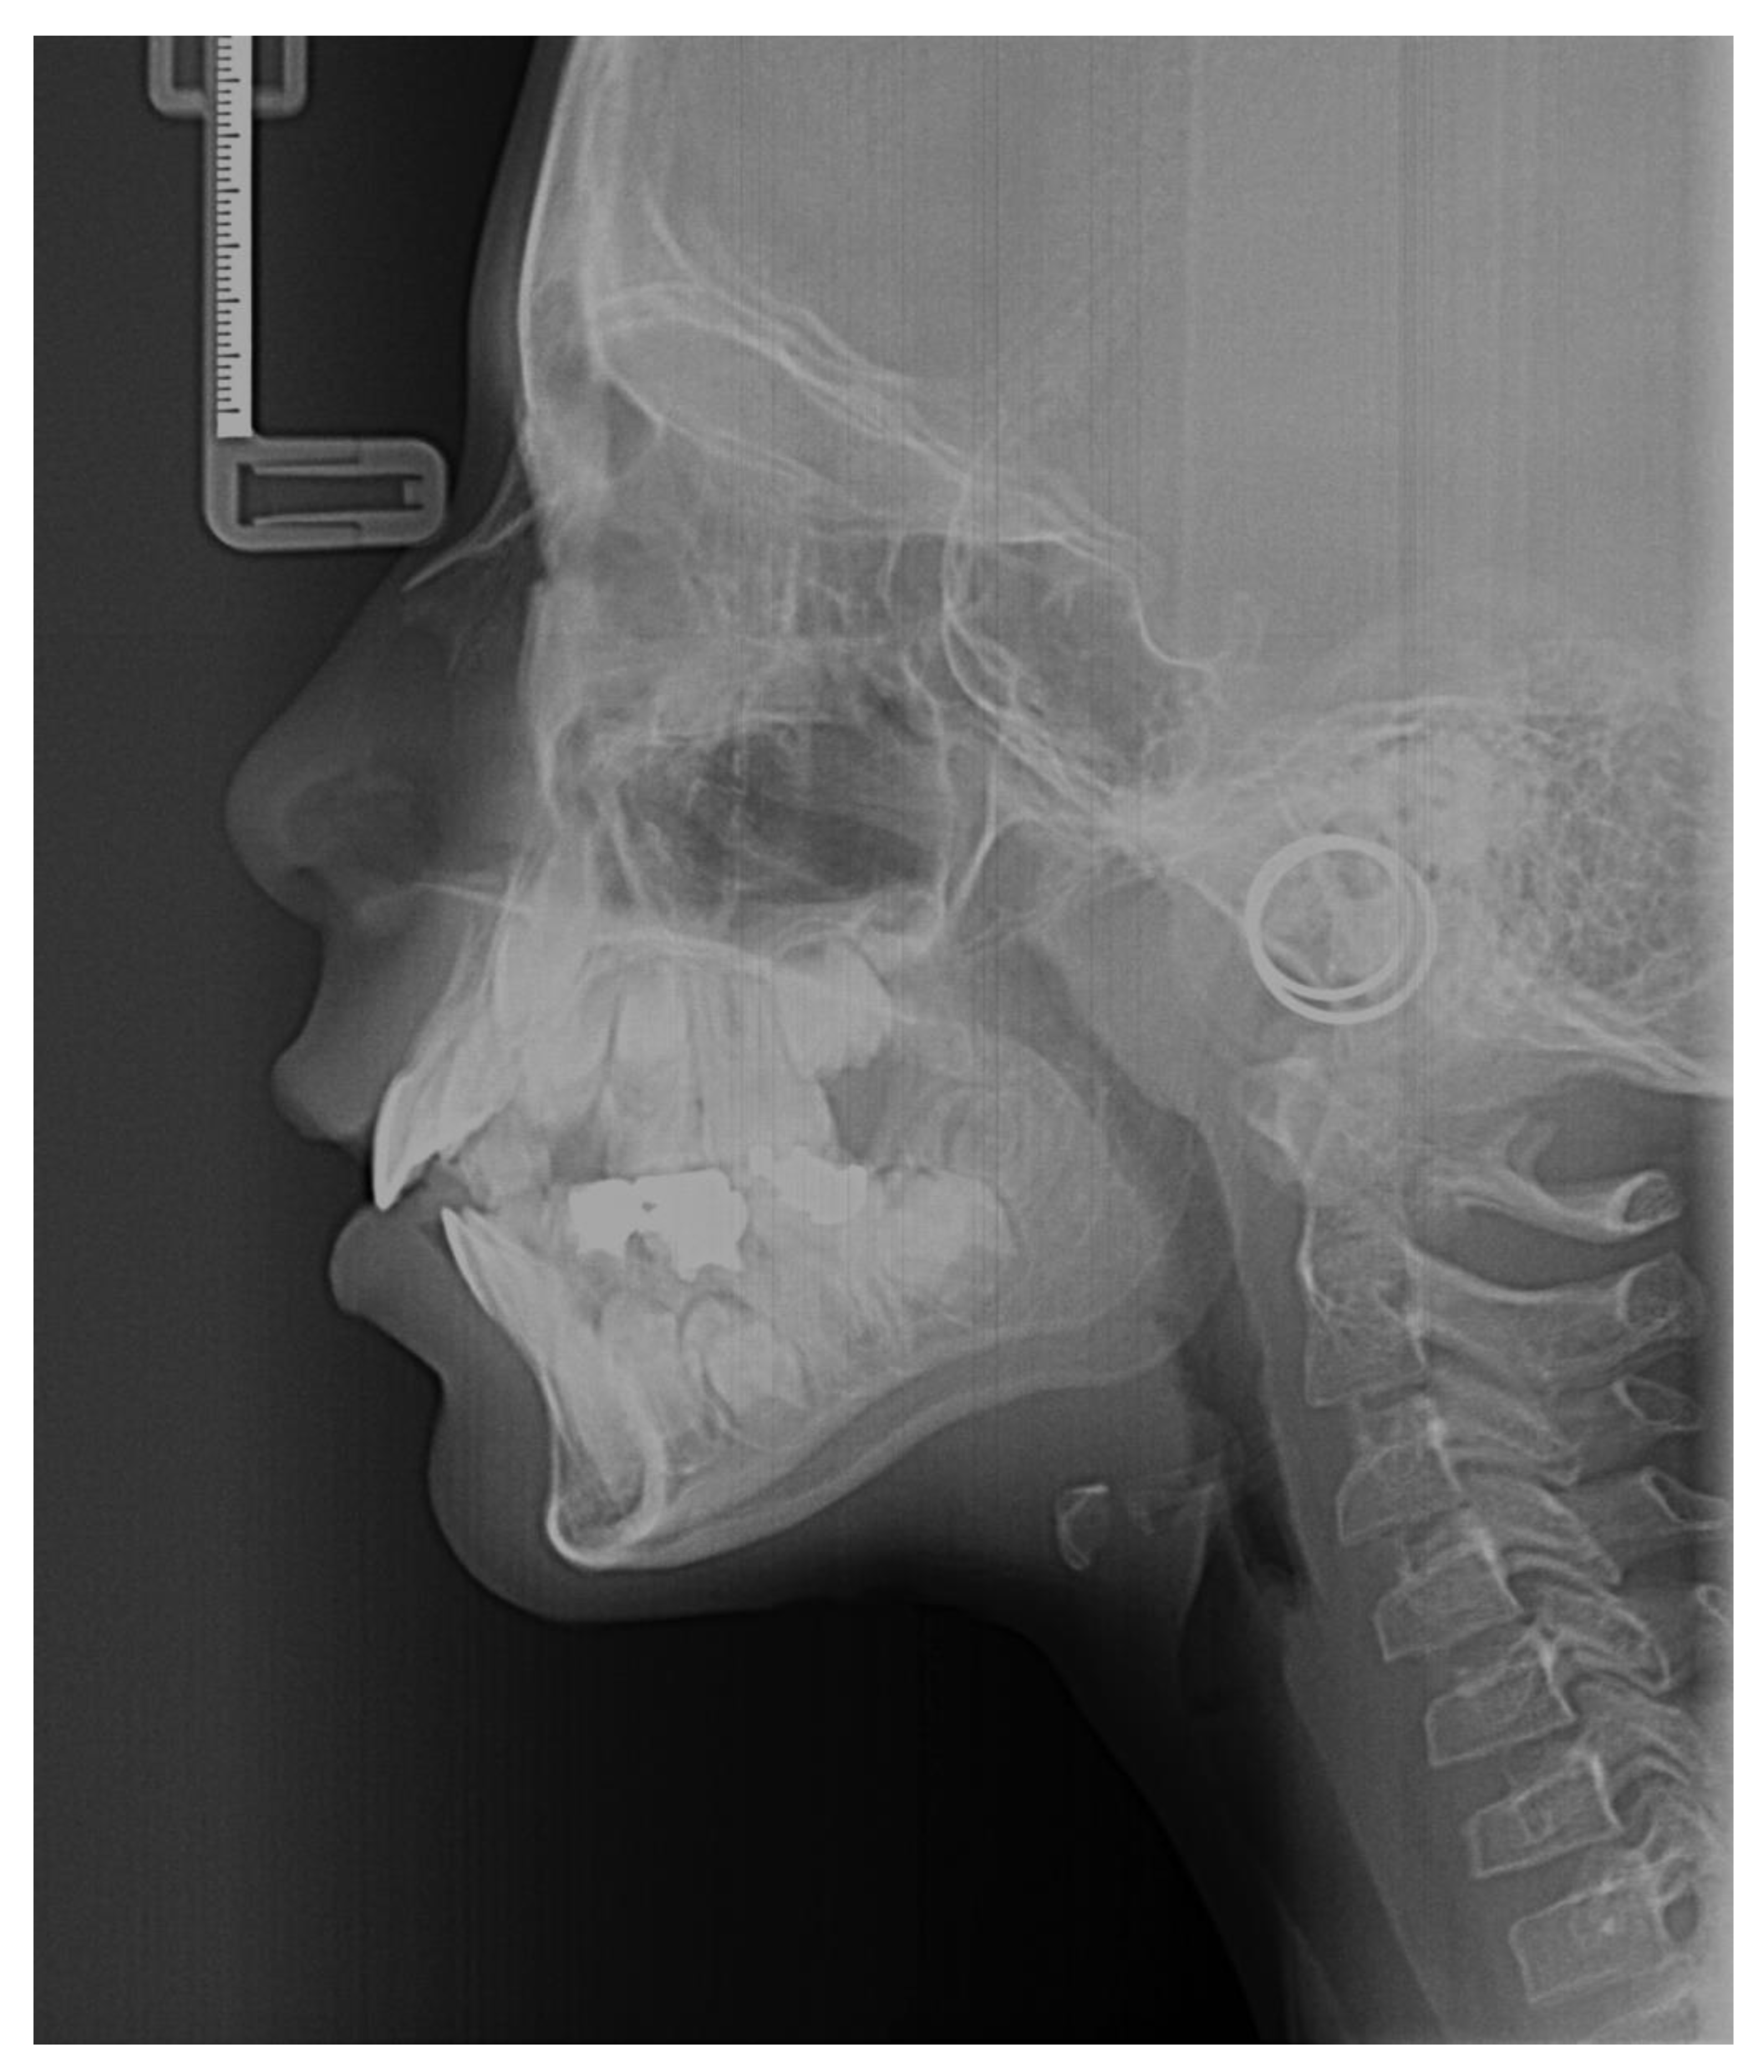

2. Cervical Vertebral Maturation Method

3.5. Dataset